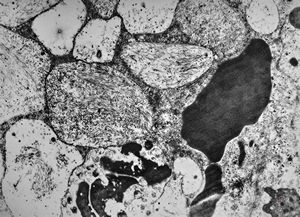

M, 1y. | gangliosidosis - liver